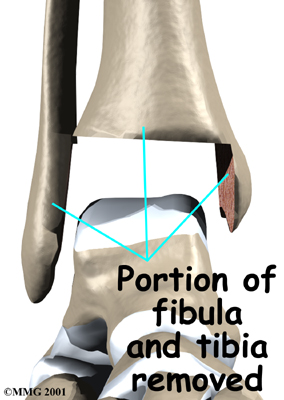

Each artificial ankle prosthesis is made of two parts:

- The tibial component is the part of the artificial joint that replaces the socket portion of the ankle (the top section).

- The talus component replaces the top of the talus.

The tibial component is usually made up of two parts: a flat metal piece called a metal tray that is attached directly to the tibia bone, and a plastic cup that fits onto the metal piece, forming a socket for the artificial ankle joint. The talus component is made of metal and fits into the socket of the tibial component.

X-rays will be taken several times after your surgery to make sure that the artificial joint has not moved out of place and that the fusion between the fibula and the tibia is forming. When the uncemented type of implant is used, X-rays also help determine whether bone is attaching to the metal implant.